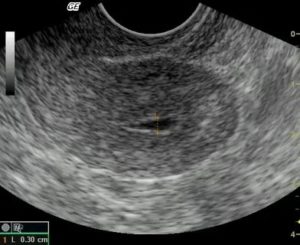

Чтобы выявить скопление жидкости, обязательно ультразвуковое обследование. Только оно способно точно определить серозометру.

Что делать, для обнаружения патологии? Существует ряд заболеваний, которые по своей симптоматике очень похожи между собой. Для выявления серозометры используются такие методы диагностики, как УЗИ и гинекологический осмотр.

Патология долгое время женщину может не беспокоить. Признаки чрезмерного образования секрета в маточной полости нередко выявляются случайно при проведении планового или диагностического УЗИ.